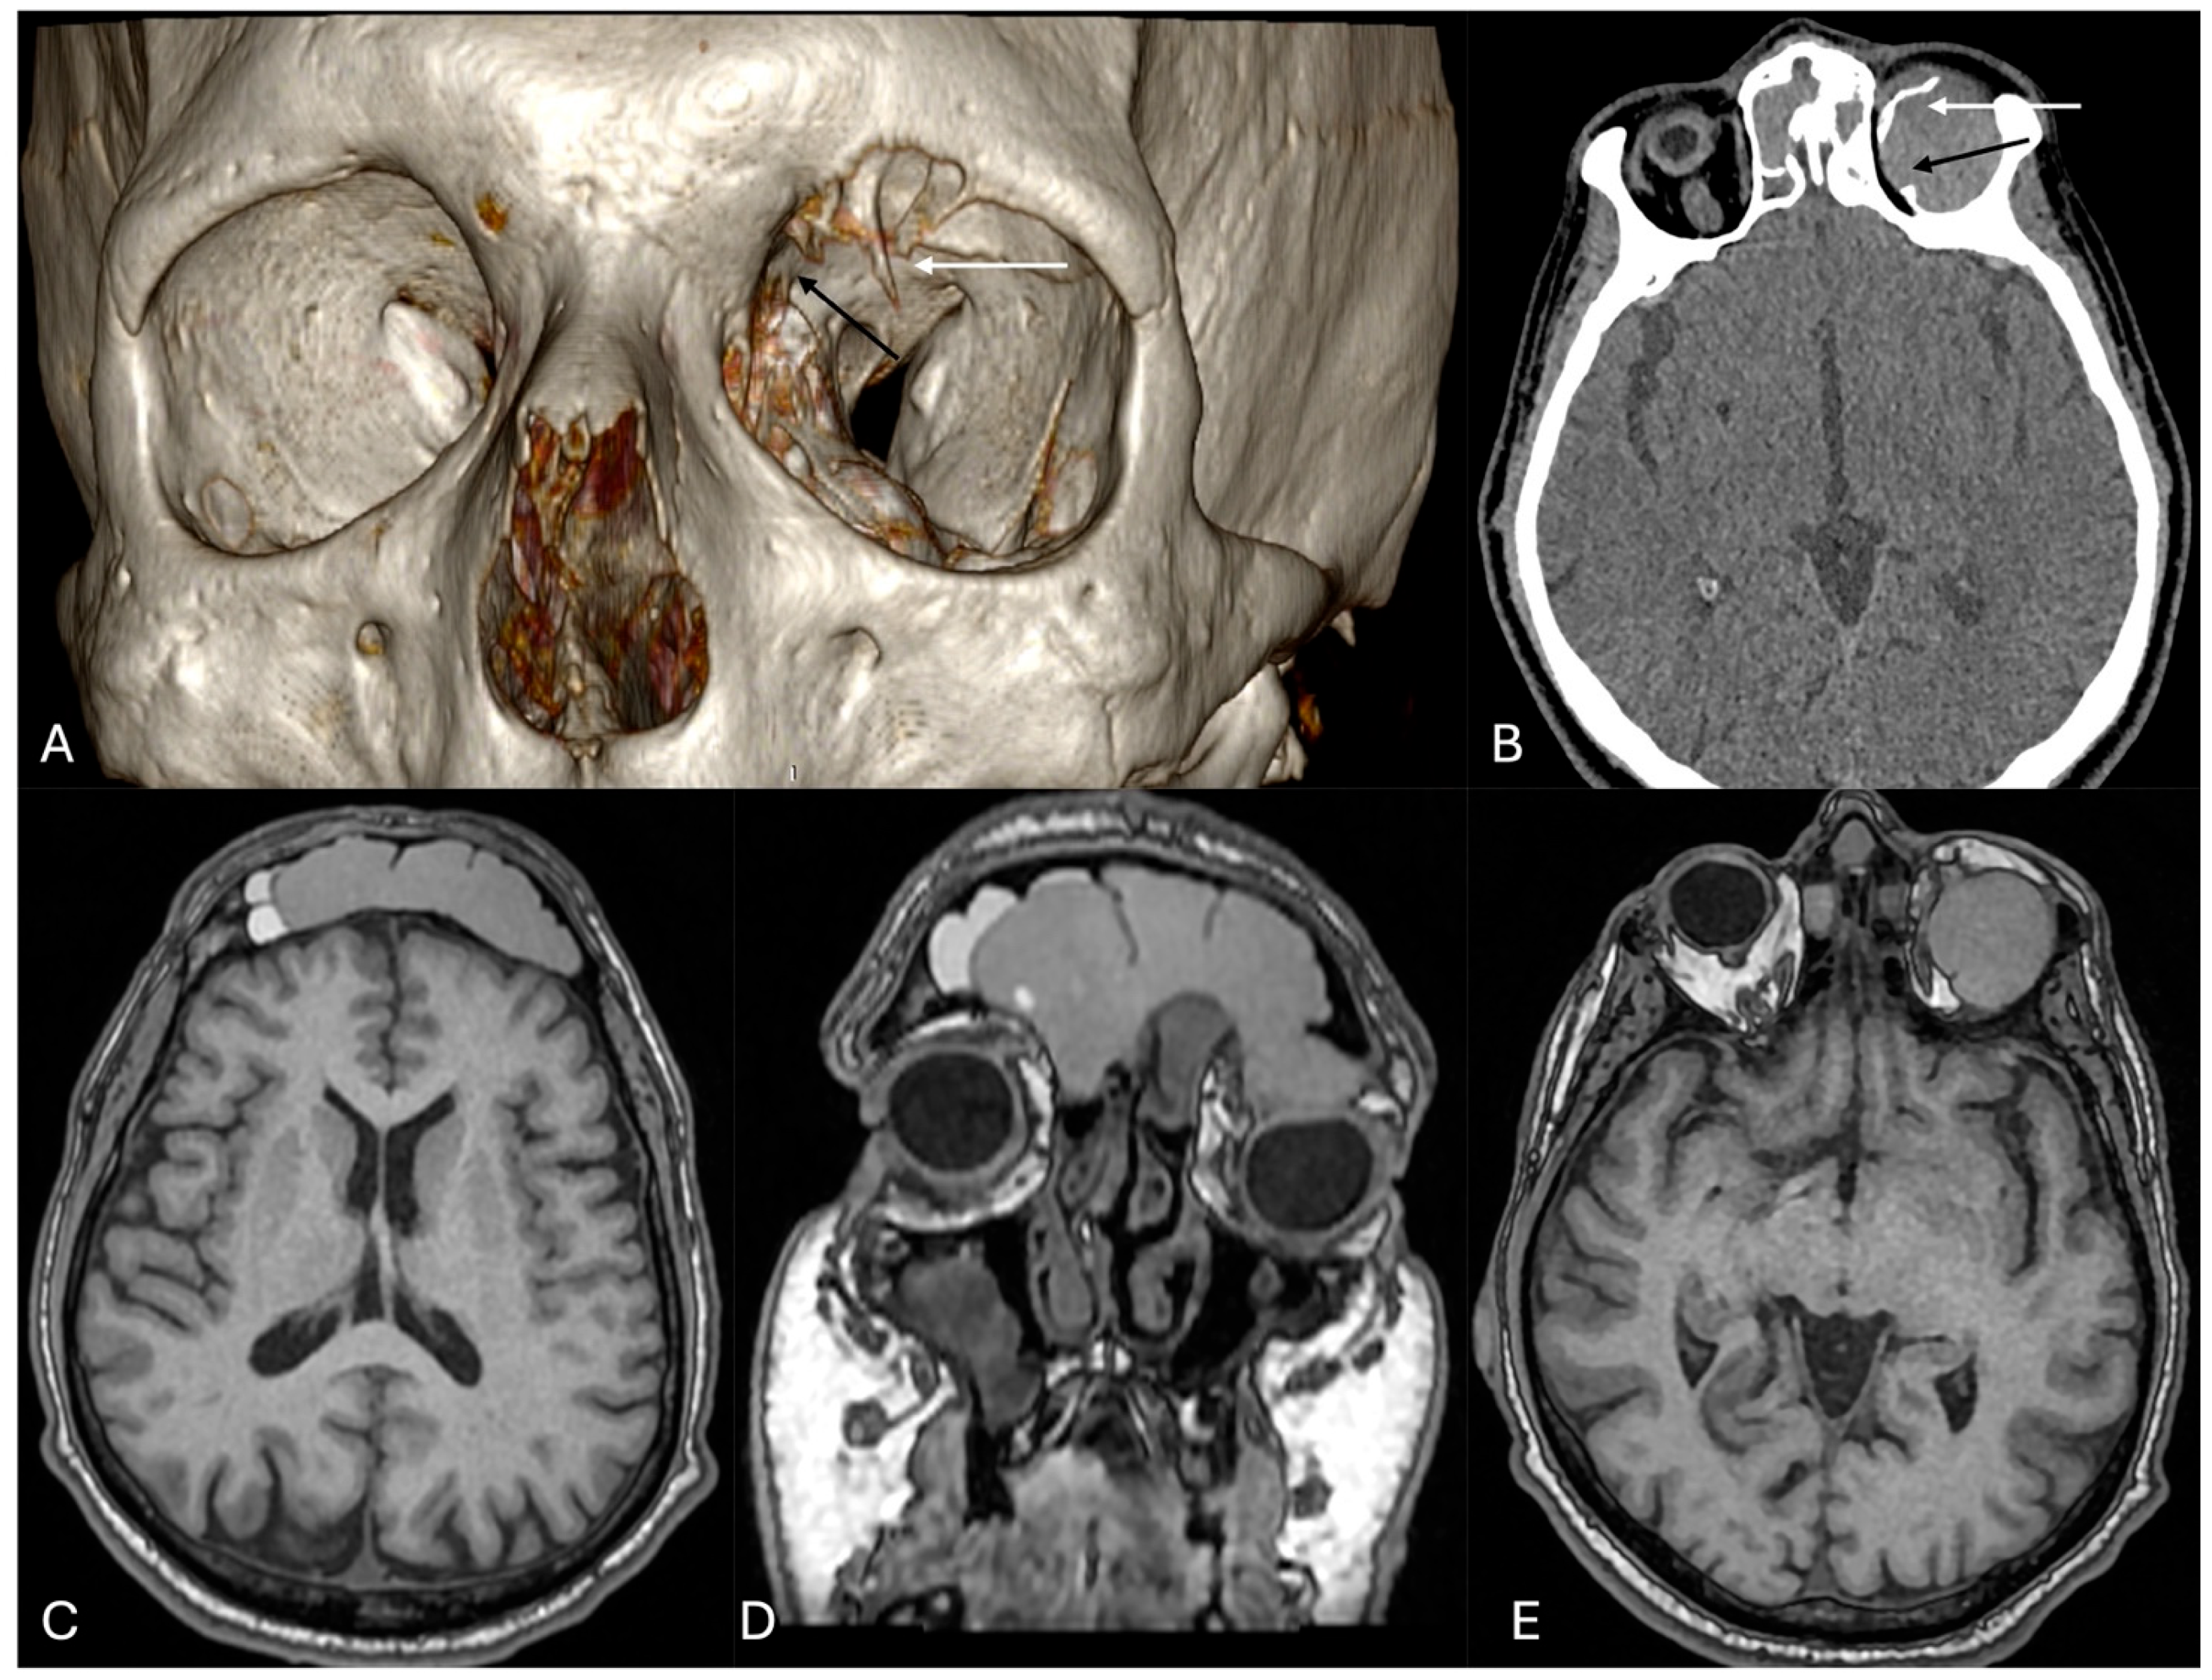

3.1. Clinical Case

3.2. Literature Review